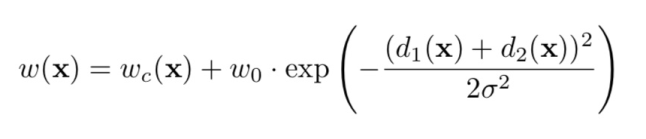

- 2、为了凸显某些像素点更加重要,作者在公式中引入了w(x)(类别不均衡)

- 对每一张标注图像预计算了一个权重图,来补偿训练集中每类像素的不同频率,使网络更注重学习相互接触的细胞之间的小的分割边界

- 权重计算公式如下:使用形态学操作计算分割边界,wc是用于平衡类别出现频率的权重, d1d1代表到最近细胞的边界的距离, d2代表到第二近的细胞的边界的距离。基于论文经验设定w0=10, σ≈5像素

- 网络的权重进行高斯分布初始化,分布的标准差为2/N2/N,N为每个神经元的输入节点数量。

- 例如,对于一个上一层是64通道的3x3卷积核来说,N=9x64